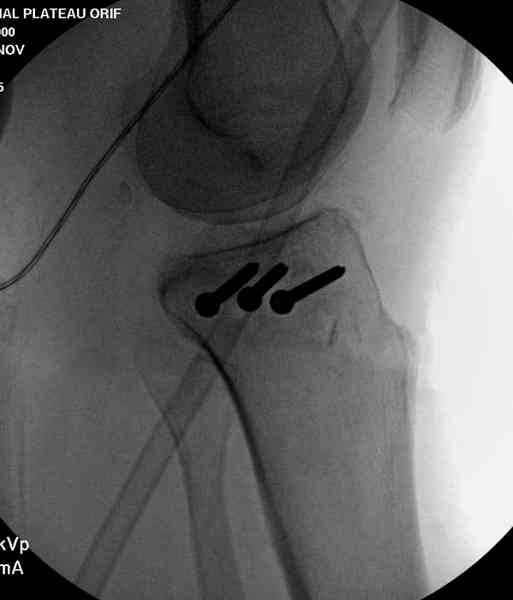

Из медиального окна можно приподнять латеральную

импрессию. Фиксация тремя параллельными шурупами в

эпифизарной части над импрессией. Создается крыша,

которая предупредит коллапс. На образовавшуюся полость - костная пластика из аутокости или синтетический заменитель. Мы применяем Osteoset в 4-5 мм диаметре таблеточки или иньекционную форму Prodens.